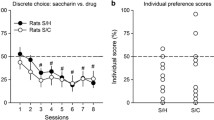

Allomorphic choice

Allomorphic results generally mirrored those from the isomorphic condition. Shown in Fig. 3, the matching NLME model successfully formalized drug choice data and revealed both the Signaled [SR = 0.29; SM = 1.12] and Unsignaled [SR = 0.21; SM = 1.10] groups were comparably sensitive to changes in relative reward rates [F(1, 171) = 19.80, p < .001] and magnitudes [F(1, 171) = 147.38, p < .001] between REMI and food. Although the two groups were not different in sensitivity to changing reward rates or magnitudes, like the isomorphic decision context, the Unsignaled group again had a higher exchange rate [Ex = 5.86; F(1, 171) = 11.90, p = .001] than the Signaled group [Ex = 3.16]. The exchange rate parameters suggest that an unsignaled food pellet was a better substitute for an unsignaled REMI infusion (1 pellet was equal to a 5.86 μg/mg unsignaled infusion) than for a signaled REMI infusion (1 pellet was equal to a 3.16 μg/kg signaled infusion). Similar to the isomorphic condition, a signaled REMI infusion had greater subjective reward magnitude as indicated by the unsignaled pellet having a lower Ex value (i.e., was a worse substitute) relative to the ability of an unsignaled pellet to substitute for an unsignaled REMI infusion.

Mean (± SEM) proportion choice of Option A for the Signaled (a) and Unsignaled (b) groups as a function of the relative reward rates for Option A in the allomorphic choice context. The x-axis is logged for improved visualization. c Mean (± SEM) parameter estimates from the matching model. d Example RL model fit. Hatched lines denote changes in the reward magnitude for Option A of 3, 1, and 10 μg/kg from left to right. e Median (± interquartile range) parameter estimates from the RL model. Note: β values are scaled according to the right y-axis. n = 8 for panels a, b, c, and e for each group

RL models also successfully parameterized allomorphic drug-associated decision-making (Fig. 3d; ΔAIC = − 640 from a chance model) and corroborated matching model assumptions. Reformulating RL value-updating equations as relative to each commodity in combination with the matching-derived exchange rates (Eqs. 4 and 5) produced substantially improved AIC values relative to a base RL model [ΔAIC = − 348.73; see SI]. Subsequently adding additional learning rate parameters dependent upon choice outcome (win versus loss) and option-dependent perseveration parameters also produced the best overall AIC values. Parameter estimates from the best fitting model are shown in Fig. 3e. RL parameters showed no group effects, but α values for wins were significantly higher than losses across both options and groups [Z = 3.10, p = .002], and the inclusion of matching-derived exchange values accounted for a group effect a priori, as supported by AIC values.